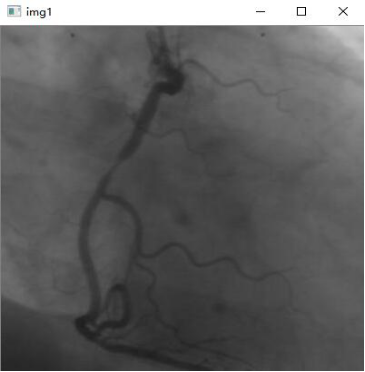

三:医学检测

医学信息处理,即对医学信息的处理,医学信息处理过程中借助计算机技术,具有非常高的应用价值,在提高信息处理准确度的同时,也极大地增强了信息处理的效率,为广大患者与患者家属创造更为人性化的就医环境。

利用计算机的先进技术可以对医学图像进行处理,然后更加方便地得到图片上蕴含的信息,从而进行正快速地得到我们想要得到的信息。

这里是用python+opencv进行医学图像识别,借助计算机技术帮助医生对医学图像进行有效地分析。